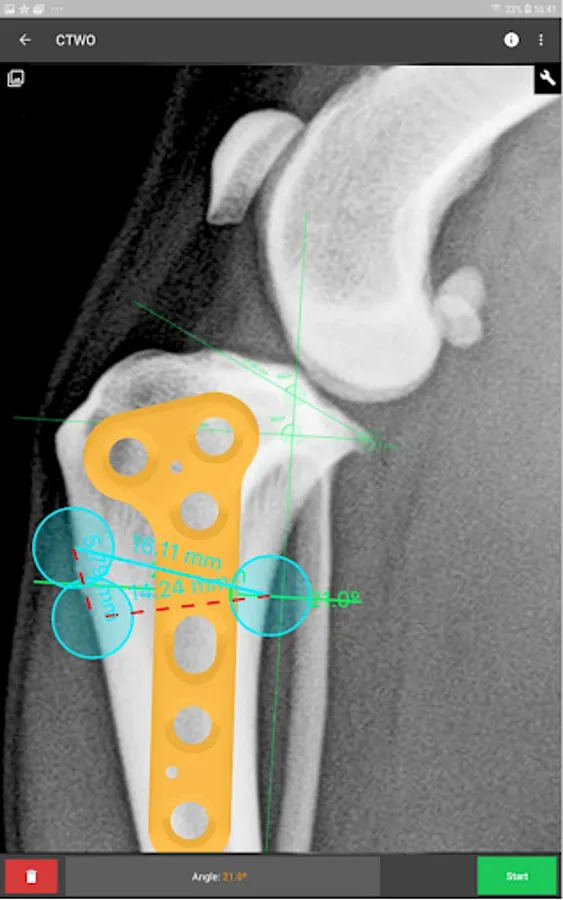

This is a useful tool for traumatology and orthopaedic surgical planning veterinary, including advanced techniques for treat canine anterior cruciate ligament (ACL) injuries (TPLO and CTWO).

3. Tools:

c) Angle measure/Triangle draw.

e) Wedge cut, CTWO and angular osteotomies.

l) CTWO plates